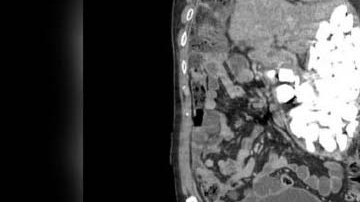

¿Malestar estomacal? Cómo identificar si se trata de una hernia de hiato por El Diario 04 de Mayo de 2019

¿Por qué se produce el cáncer de estómago y cuáles son sus tratamientos? por El Diario 21 de Marzo de 2019

Paciente tenía dos kilos de piedras, tapas de botellas y monedas en el estómago por El Diario 20 de Febrero de 2019

Médicos extraen más de un centenar de clavos del estómago de un hombre por El Diario 23 de Octubre de 2018

Descubren su cadáver gracias a un árbol que creció por una semilla que tenía en el estómago por El Diario 21 de Septiembre de 2018